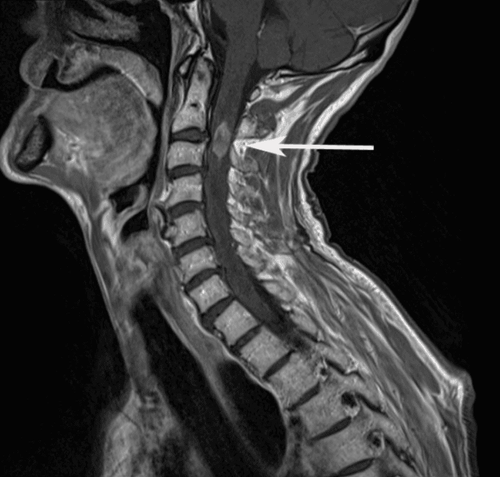

Tủy cổ là cấu trúc thần kinh trung ương kết nối các thông tin dẫn truyền từ não xuống dưới để điều khiển cử động tay chân. Chấn thương cột sống cổ có hai loại hình tổn thương, trong đó tổn thương gây dập phù tủy cổ là thương tổn khá nặng, khiến bệnh nhân yếu tay chân, trong một số trường hợp tổn thương trên cao có thể gây ngưng thở.

Việc chẩn đoán loại tổn thương này, bác sĩ thường hay cho chỉ định chụp MRI cột sống cổ. Tuy nhiên khi phát hiện có dập tủy cổ thì có hai phương pháp điều trị chính: